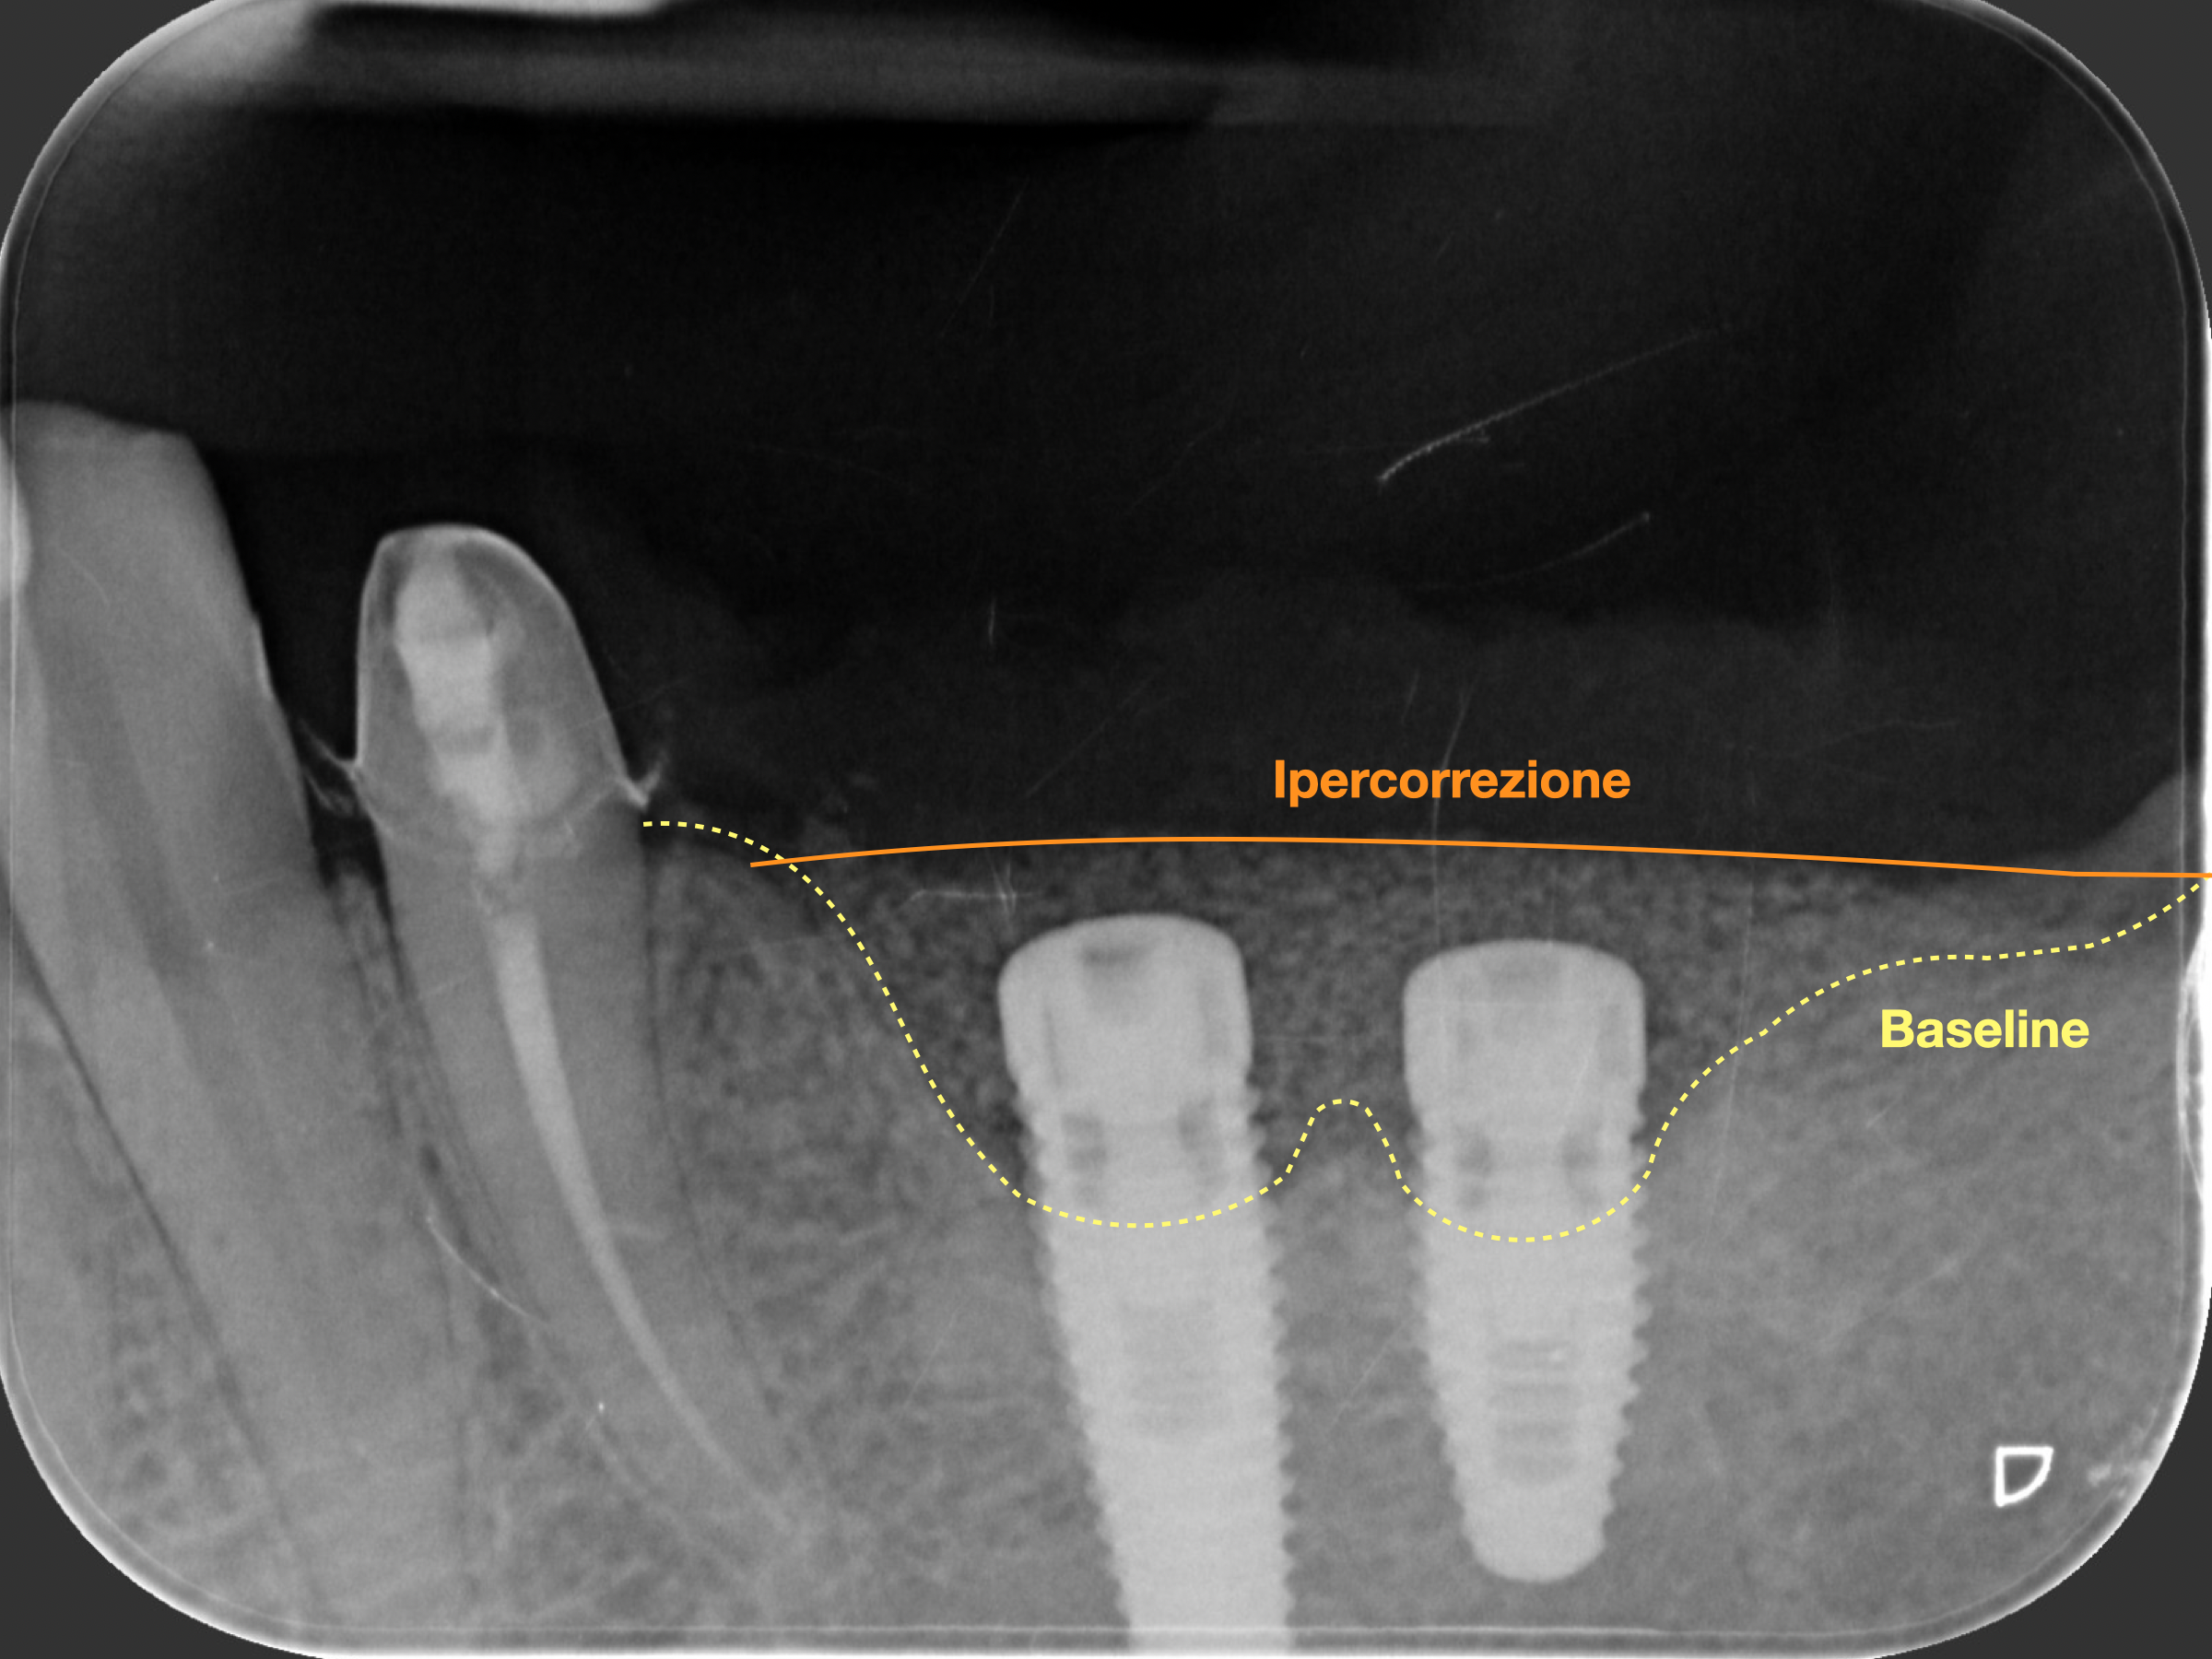

Nel caso clinico che presentiamo, è stata eseguita una GBR (Guided Bone Regeneration), rigenerazione ossea guidata:

📸 Radiografie e foto mostrano chiaramente il recupero del supporto osseo e la stabilità dell’impianto a distanza di mesi.